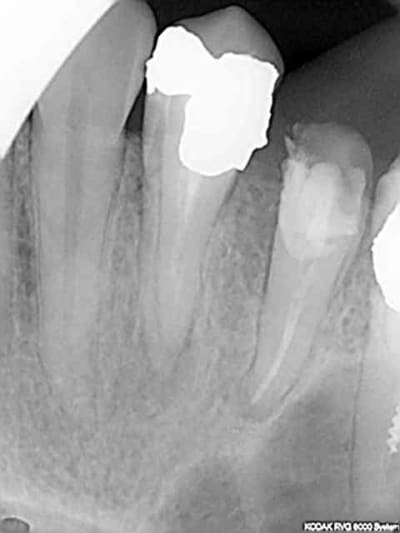

Ca m'arrive de foirer mais rarement, ici racine distale de 16 manque 2 mm. je n'essaie pas de forcer outre mesure et d'arriver à tout prix à l'apex.

Capture d e cran 2015 07 30 16.30 - Eugenol

T'es fâché avec les racines DV des 1ères molaires sup ?

:)))